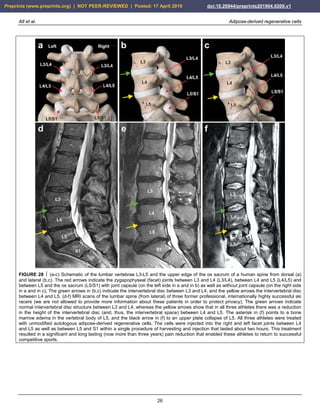

year after performing a standard procedure without application of

years previously. Figure 24a shows an arthroscopic view

plateau was still present (white asterisk in Fig. 24a).

24a). Figure 24b shows the situation after arthroscopic

removed (black asterisk in Fig. 24b). Then, the right knee

obtained from 50 g of abdominal adipose tissue. A control

tibial defect (white asterisk in Fig. 24c) and of the femoral

cartilage (arrows in Fig. 24c). The left knee of the same

damaged cartilage and drilling of small holes into the

somewhat uneven, overshooting fibroblastic scar

FIGURE 24 ïŁŠ Example of successful application of unmodified

autologous adipose-derived regenerative cells (UA-ADRCs) for

treating cartilage defects. The panels show arthroscopic views of

the right (a-c) and the left (d) knee of a male, 51-year-old patient

who presented with recurring and increasing pain in both knee

joints during walking and other activities. (a) Third-degree

damage to the right tibial plateau (white asterisk) after a tibial

chondrocyte transplantation that had been performed three years

previously, as well as considerable osteoarthritic damage of the

femoral cartilage (black asterisk). (b) Situation of the right knee

after arthroscopic removal of the failed chondrocyte transplant

(white asterisk) as well as 'mushy' and damaged cartilage

structure on the femoral condyles before it was removed (black

asterisk). (c) Situation of the right knee one year after

arthroscopic removal of damaged cartilage and a single

application of UA-ADRCs isolated from 100 ml lipoaspirate,

showing complete healing of the tibial defect (white asterisk) and

of the femoral parts, with formation of new whitish cartilage that

shows a sharp demarcation border to the existing old and more

yellowish cartilage (arrows). (d) Situation of the left knee one